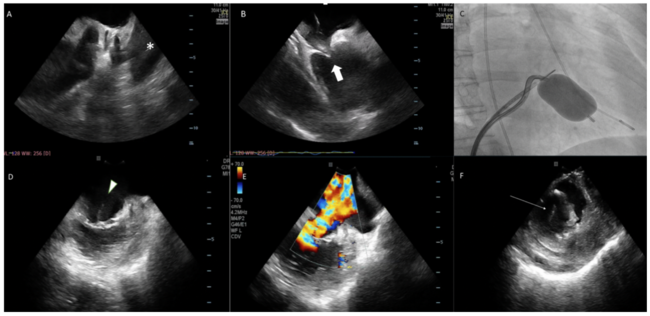

A 67-year-old woman was referred for PMC due to severe mitral stenosis. Pre-operative TEE showed favorable mitral anatomy. Under local anesthesia, ICE (ViewFlex Xtra; Abbott) was first positioned at the main pulmonary artery to exclude left atrial appendage (LAA) thrombus (Figure 1A). Transeptal puncture was guided by ICE at the right atrium (Figure 1B), aiming at inferior-posterior puncture to allow for more direct access to the mitral valve. An Inoue wire was then advanced into the left atrium under full heparinization. After dilatation of the interatrial septum with a 14 Fr dilator, the ICE catheter was advanced into the left atrium through the same transseptal site. The Inoue balloon was directed across the mitral valve and inflated to 24 mm under ICE and fluoroscopic guidance (Figure 1C). Immediately after balloon inflation, a giant V wave was noted. ICE at the left atrial as well as the right ventricular position revealed rupture of the mitral chordae causing severe mitral regurgitation (Figure 1D and 1F, Videos 1-3). Patient remained stable and was referred for early mitral valve surgery.

This case illustrated a typical case of ICE-guided PMC, which improved safety of the procedure by excluding left atrial thrombus, guiding transseptal puncture, and immediate detection of complication without the need for general anesthesia. ICE should be used during PMC to enhance procedural safety and enable early detection of complications should they arise.